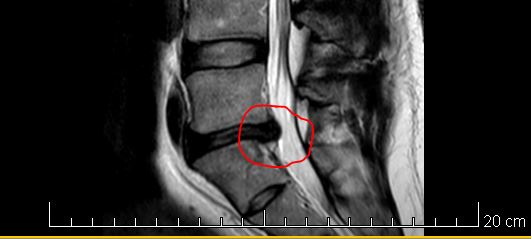

Ach Anja, mal sehn was sie machen. Bei meinem letzten Besuch wollten sie mich eigentlich schon operieren, statt dessen gab´s nur ne PRT Spritze. Die Spritze sollte als Test dienen, also wenn die Spritze eine Wirkung zeigt, dann ist eine OP recht erfolgsversprechend. Ein wenig hat die Spritze geholfen. Ich werde das den Ärzten so beschreiben und was die dann mit mir machen, ich hab keine Ahnung. Ich vertraue den Göttern in weiß.

Der Wirbel muss nicht versteift werden, soviel kann ich dir sagen. Ich werde dort morgen aufschlagen und dann werd ich sehen was passiert, bin recht entspannt und lass alles auf mich zukommen. Am Bandscheibenvorfall ist noch keiner gestorben.

@Turbo M Wenn der Wirbel nicht versteift werden wird dann machen die das zu 99% endoskopisch. Das vorgewölbte Gewebe wird entfernt und je nach Beschädigungsgrad eine neue Bandscheibe eingesetzt. Sorry ich habs gestern nicht mehr gelesen

Das ist ein relativ kleiner Eingriff. Ich wünsche dir das alles gut klappt und du bald wieder ganz beweglich bist

Also erstmal danke, danke, danke @all für die lieben Genesungswünsche. Ich bin vorerst wieder zu Hause. Heute hab ich nur einen Termin bekommen, weiter nix. Das hätte man auch telefonisch erledigen können aber gut. Montag muss ich wieder hin, dann findet das Anästhesiegespräch statt und nächsten Donnerstag wo unsere kleine Fee Cordula Grün zum Folierer bringt geht´s auch bei mir los, dann werde ich für ne gewisse Zeit entweder teilweise oder vollständig eingeschläfert.

Der Arzt, mit dem ich mich heute unterhalten hab, hat mir auch schon gesagt, dass das der Eingriff nix großes ist, genau wie Anja auch schon geschrieben hat. Ich bin da auch recht entspannt.

Und diese minimal invasive OP ist für die eine Routineübung. Dauert 30-45 Min

Entweder wie gesagt perkutan endoskopisch von der Seite oder mikrochirurgisch, bei beiden nur ein klitzekleiner Schnitt max 2 cm

... und der 5. Lendenwirbel heißt Cordula Grün